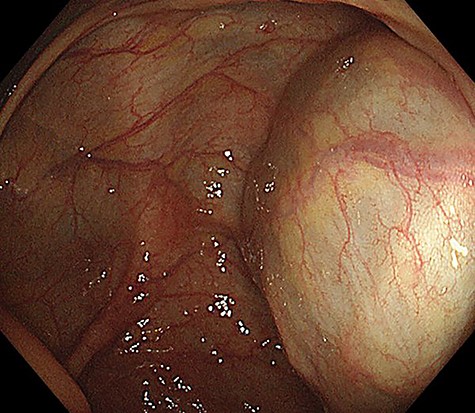

A 49-year-old woman presented with painless swelling in her right inguinal region. She had a history of caesarian section and no history of infantile inguinal hernia. Physical examination revealed a soft egg-shaped mass extending from the right inguinal region to the labia majora. The mass was seen as a protrusion when the patient was in the standing position, while it disappeared when the patient was in the lying position. Ultrasound revealed a well-defined hypo-echoic elongated mass that extended from the superficial inguinal canal, with no solid component (Fig. 1). Computed tomography (CT) showed that 55 × 34 × 95 mm oval fluid collection located at the right inguinal region near the cecum and retroperitoneum in the abdominal cavity (Fig. 2). Total colonoscopy found no mucosal abnormalities from the cecum to the rectum; however, a mass of tissue pushed the cecal wall from outside (Fig. 3). This hinted toward a large HCN, appendiceal tumor or retroperitoneal tumor; we decided to attempt a combined approach of conventional and laparoscopic methods for diagnosis and treatment of the swelling. We used three ports (12, 10 and 5 mm; Fig. 4) for our laparoscopic approach. We placed a 12 mm laparoscopic trocar into the umbilicus for CO2 insufflation of the pneumoperitoneum. Endoscopic intraperitoneal observation revealed that the mass was distant from the cecum and outside the peritoneum (Fig. 5). The tumor was large and was not completely observed using only an intra-abdominal approach. Therefore, we used a combined approach, which was the conventional method with a skin incision in the inguinal region in addition to the intra-abdominal method with laparoscopic approach. The tumor could be resected without any damage by observing from both directions (Fig. 6). We adopted the Direct Kugel Patch (ONFLEX®, C.R. Bard, Inc., USA) for the vulnerability of the posterior wall of the inguinal canal. Histopathological examination revealed that the mass contained single-layered mesothelial cells and no tumor or endometriosis. Based on imaging, histopathology and operative findings, we diagnosed her with an HCN. The patient recovered and did not have any postoperative complications, and she was discharged from hospital on postoperative day 6. She had no recurrence of hernia or hydrocele until 16 months postoperatively.

Colonoscopy image showing an unknown tissue mass that is pressed against the cecal wall from the outside.